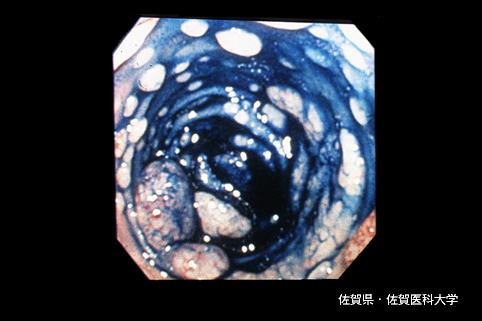

症例提示(所在地,施設名等): 佐賀県・ 佐賀医科大学 (Dr.水口)

疾患(病理主体)の分類悪性リンパ系腫瘍/悪性リンパ腫

部位(臓器別)大腸/回盲部

検査方法内視鏡

病変の最大径(ミリ)20〜24

多発腫瘍(同一臓器)有(同時性)